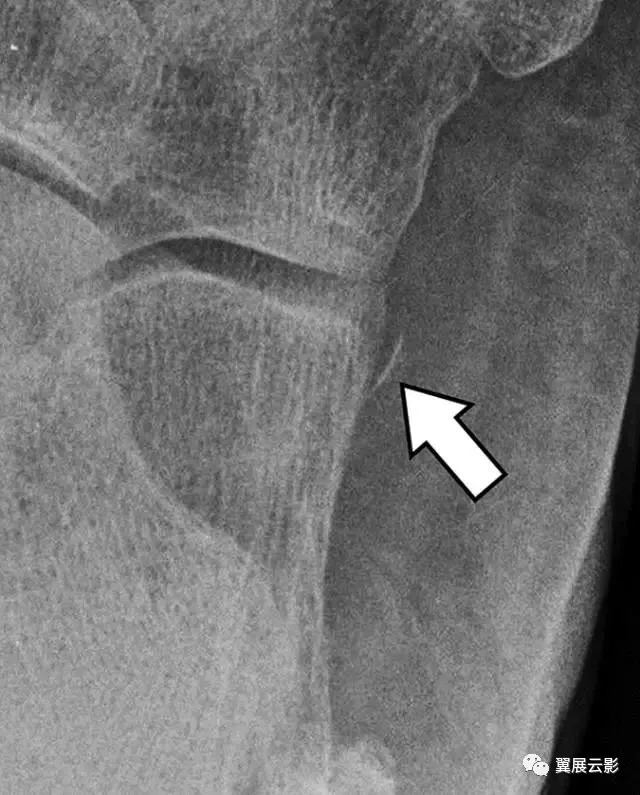

图10A -21岁的男性篮球运动员,脚外侧疼痛。A,脚的倾斜视图的特写镜头显示线性骨头(箭头)接近跟骰关节。

图10B- CT图像显示撕脱性骨折(椭圆形)对应于背侧跟骨韧带的近端附着。